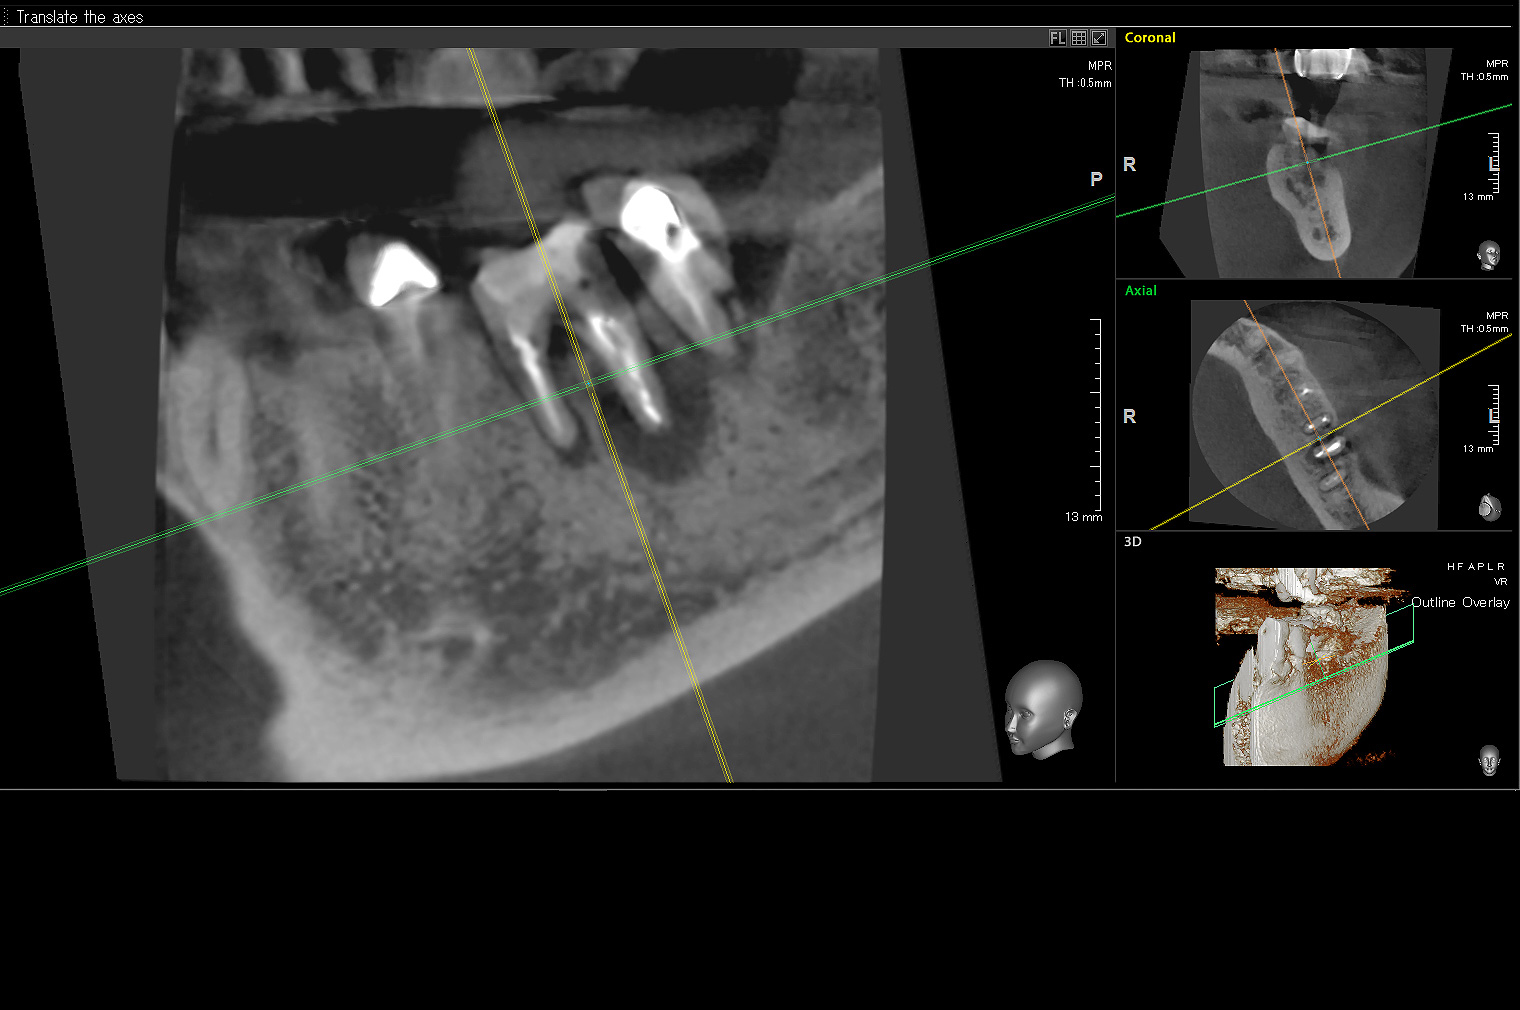

いなば歯科では歯科用CTやマイクロスコープ(歯科用顕微鏡)を使用し「出来るだけ自分の歯を残していく治療」を行っております。